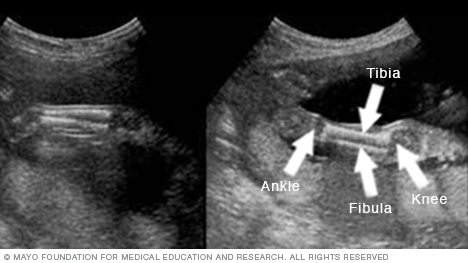

Below are images of the lower legs. The knee is on the right side of each image, and the ankle is on the left. You also can see the shinbone, called the tibia, and the small leg bone on the outside of the ankle, called the fibula.